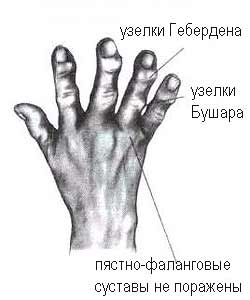

Симптомы и лечение остеоартроза узелков Гебердена: фотогалерея